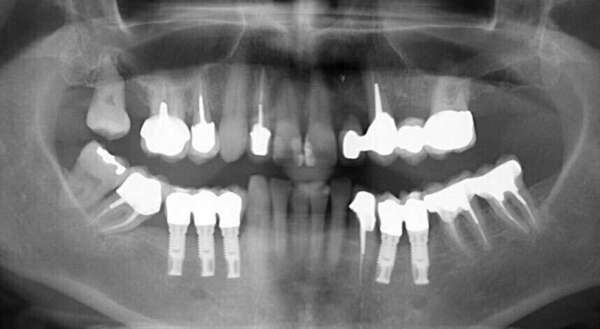

Polycaries et grande reconstitution prothétique